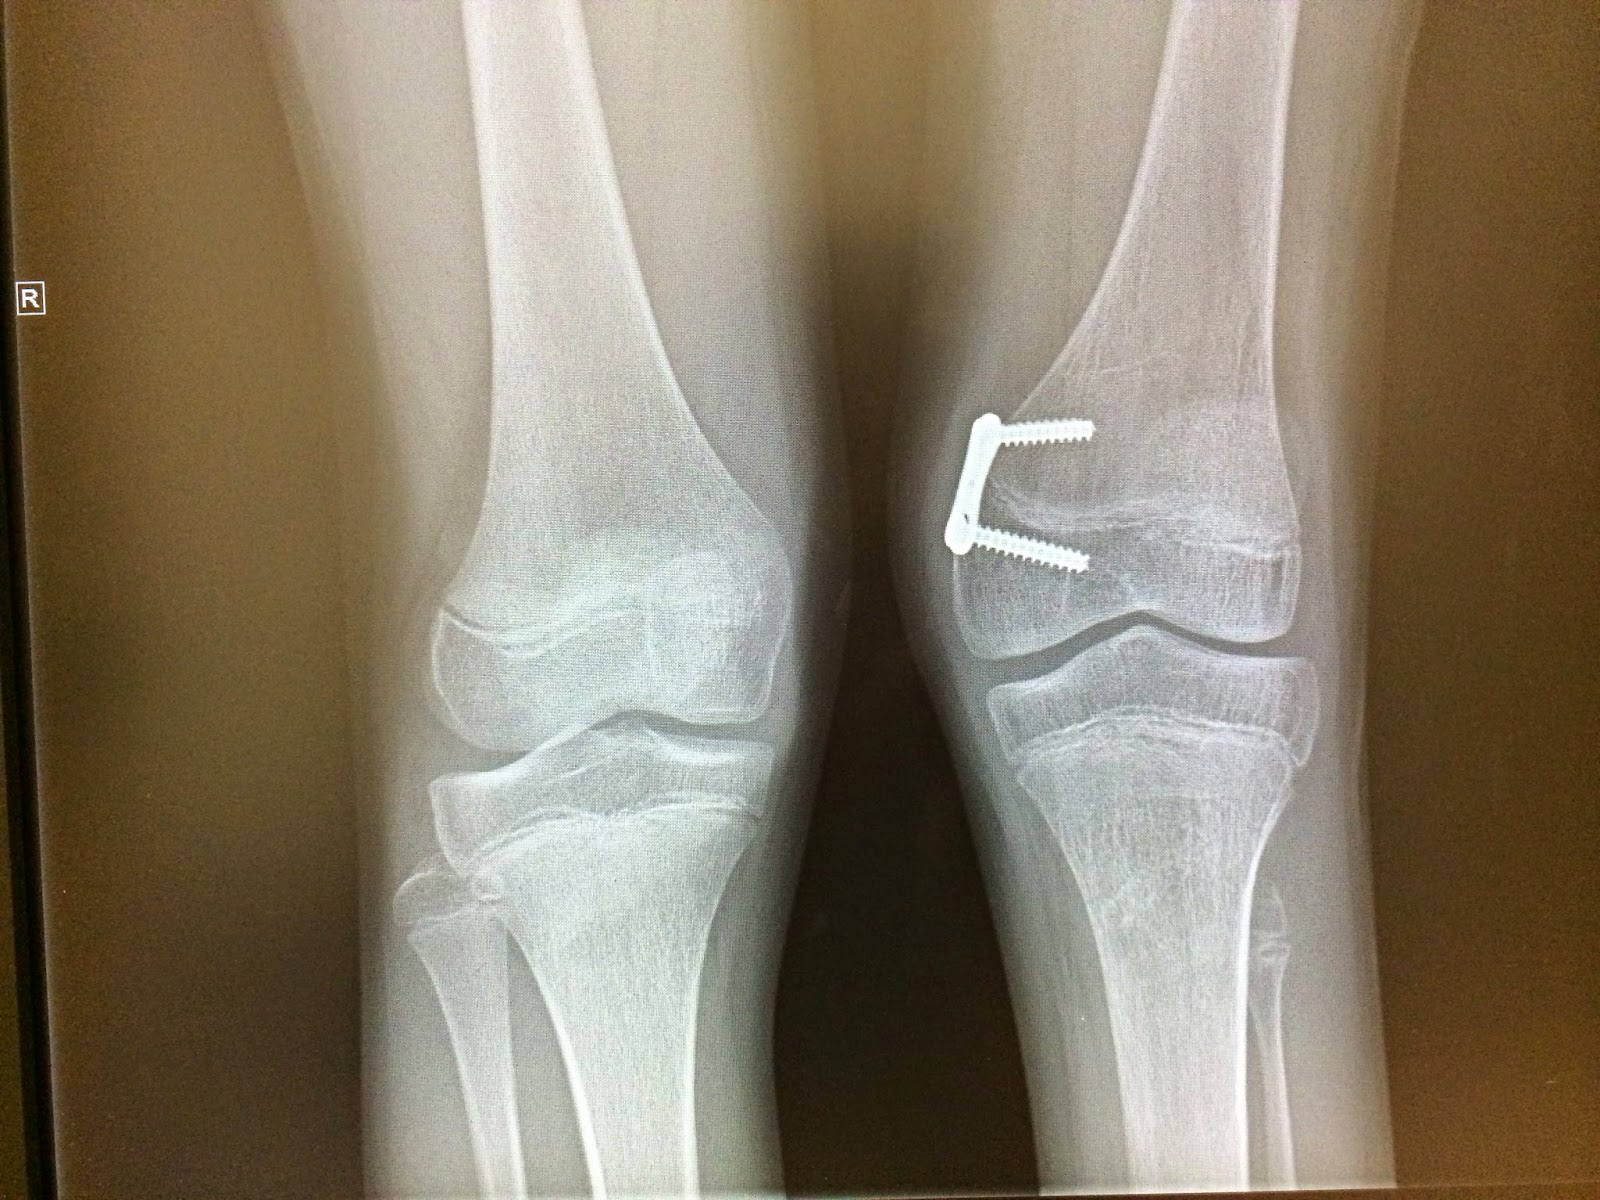

Leg Length Discrepancy Surgery Growth Plate . In patients with leg length discrepancy due to premature epiphyseal closure, the extent of shortening can be predicted based. For discrepancies greater than 3cm, however, limb lengthening may be an effective treatment choice. The limb length discrepancy will gradually lessen as the opposite leg continues to grow and catch up. Leg length discrepancy is a common condition that may be caused by a congenital defect, disruption of the physis, or a paralytic disorder and presents with limb length. This procedure slows the growth of the opposite leg or arm by altering the activity of the growth plate, thereby allowing the affected limb to “catch up” by the end of growth. This will not instantly fix. The surgeon may place metal staples, or a. Guided growth surgery (epiphysiodesis) is a way to temporarily or permanently halt the growth of the longer leg, giving the shorter leg a chance to. The growth plate fusion procedure.

The limb length discrepancy will gradually lessen as the opposite leg continues to grow and catch up. In patients with leg length discrepancy due to premature epiphyseal closure, the extent of shortening can be predicted based. Leg length discrepancy is a common condition that may be caused by a congenital defect, disruption of the physis, or a paralytic disorder and presents with limb length. The growth plate fusion procedure. The surgeon may place metal staples, or a. This will not instantly fix. Guided growth surgery (epiphysiodesis) is a way to temporarily or permanently halt the growth of the longer leg, giving the shorter leg a chance to. For discrepancies greater than 3cm, however, limb lengthening may be an effective treatment choice. This procedure slows the growth of the opposite leg or arm by altering the activity of the growth plate, thereby allowing the affected limb to “catch up” by the end of growth.

Leg Length Discrepancy Surgery Growth Plate Leg length discrepancy is a common condition that may be caused by a congenital defect, disruption of the physis, or a paralytic disorder and presents with limb length. Leg length discrepancy is a common condition that may be caused by a congenital defect, disruption of the physis, or a paralytic disorder and presents with limb length. For discrepancies greater than 3cm, however, limb lengthening may be an effective treatment choice. This procedure slows the growth of the opposite leg or arm by altering the activity of the growth plate, thereby allowing the affected limb to “catch up” by the end of growth. The limb length discrepancy will gradually lessen as the opposite leg continues to grow and catch up. The surgeon may place metal staples, or a. This will not instantly fix. In patients with leg length discrepancy due to premature epiphyseal closure, the extent of shortening can be predicted based. The growth plate fusion procedure. Guided growth surgery (epiphysiodesis) is a way to temporarily or permanently halt the growth of the longer leg, giving the shorter leg a chance to.